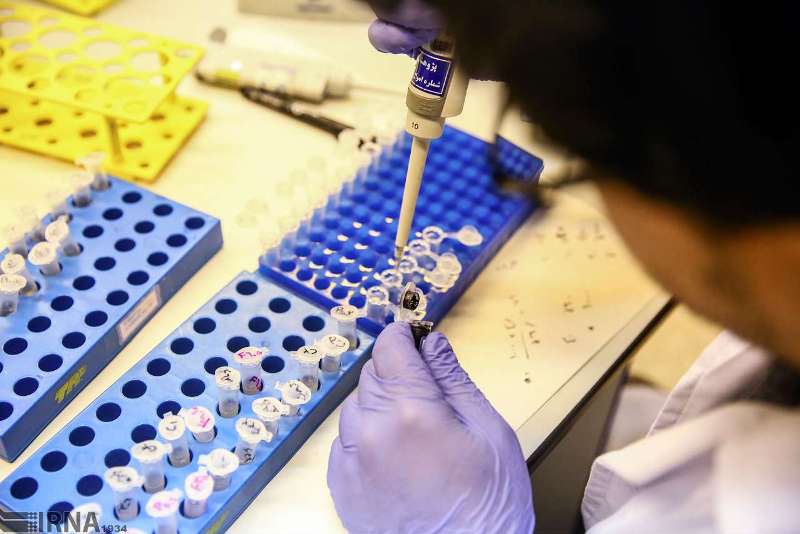

درمان این نوع آلرژی فصلی امکان پذیر است و می توانید با رعایت نکاتی ساده از آن رهایی پیدا کنید، پس نیازی نیست نگران باشید، فقط کافیست نکات زیر را با دقت مطالعه و رعایت کنید تا رفته رفته از شدت علائم حساسیت های فصلی بکاهید. لازم به ذکر است که اگر علائم شما شدید باشد در کنار رعایت نکات زیر حتما با پزشک نیز مشورت کنید و بدون تجویز پزشک هیچ دارویی را مصرف نکنید حتی اگر آن دارو بدون نسخه نیز در دسترس باشد. سامانه ی دکتر مایکو با امکان برقراری ارتباط حضوری و آنلاین با پزشکان بیمارستان ها و کلینیک ها در رفع این مشکلات و علائم شما را یاری می کند.